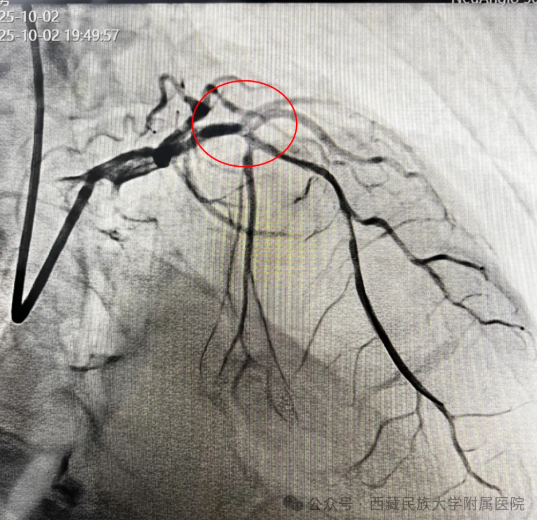

(图3:冠脉造影结果,前降支近端起闭塞)

手术在紧张而有序的氛围中展开。孙丽荣医师带领团队沉着冷静、操作娴熟,在数字减影血管造影(DSA)精准引导下,顺利将导管送至病变部位。随着闭塞血管被成功开通,心肌血流恢复灌注,患者上腹痛症状迅速缓解,生命体征逐步平稳。术后,当患者露出安心的笑容时,连续奋战的医护人员才稍稍松了一口气。这一刻,是医者仁心的最好见证,连日坚守岗位的医护人员也由衷感到欣慰。